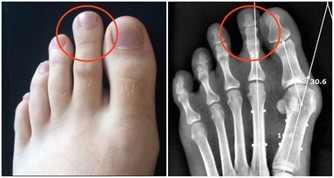

有研究表明,使用不潔的洗浴設施,有可能感染熱浴盆肺、綠膿桿菌所致毛囊炎、軍團病等疾病。